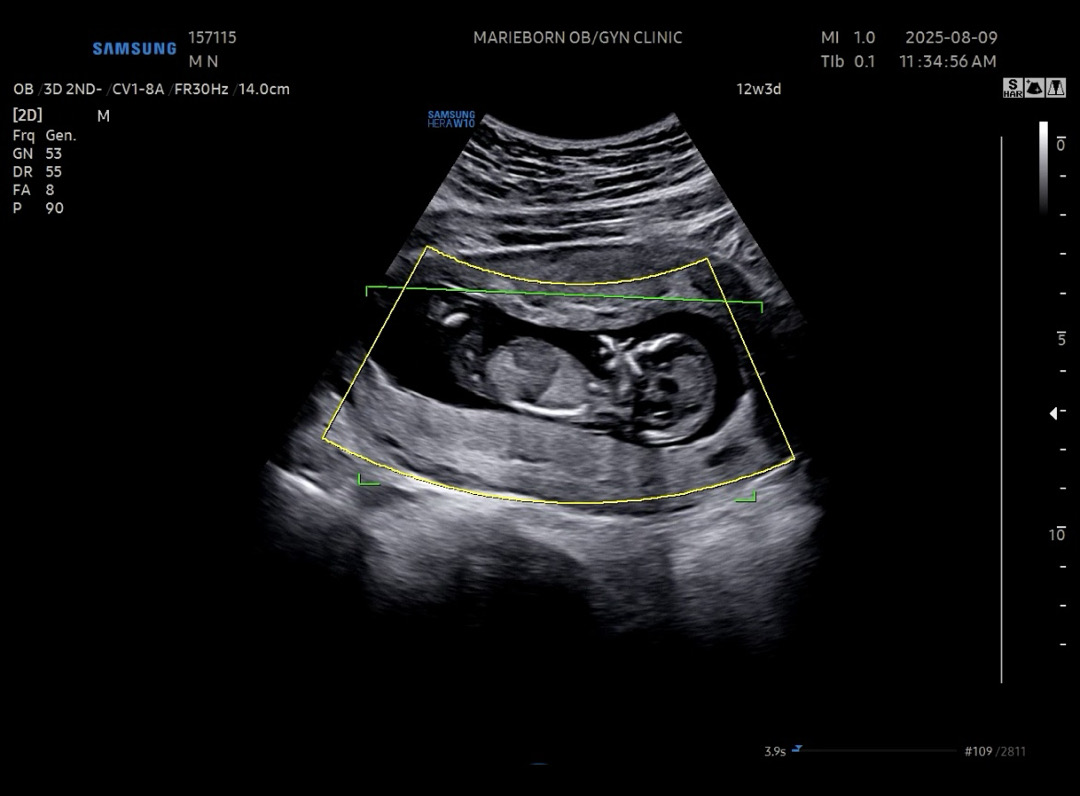

12주3일차 각도법 문의 드립니다 !!🥺

12주 3일차 각도법 문의 드려요 ㅠㅠ

사진 추가 합니다!!

아들같은데 반전가능성 아직까진있어용